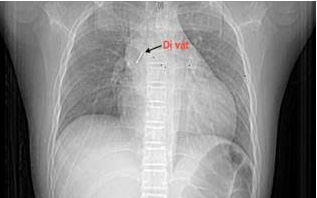

Bệnh viện kích hoạt hội chẩn liên khoa và quyết định tiến hành nội soi phế quản cấp cứu. Dị vật được phát hiện với một đầu nhọn cắm vào đoạn dưới khí quản, đầu còn lại nằm trong phế quản gốc trái.

Bác sĩ tiến hành gắp dị vật.